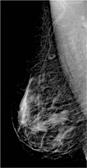

Right craniocaudal (RCC) Photos courtesy of Philips Healthcare

The MicroDose digital mammography system’s technology counts individual X-ray photons using a 50 micrometer detector element, creating very low noise and eliminating analog to digital conversion. By using matching pre- and post-collimators, only those X-rays perfectly aligned with the detector are allowed to pass through the breast, eliminating 97 percent of scatter and yielding high quality images. (See Figure 1.)